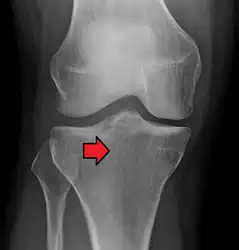

Subtle tibial plateau fracture on an AP X ray of the knee

Lipohemarthrosis due to a tibial plateau fracture